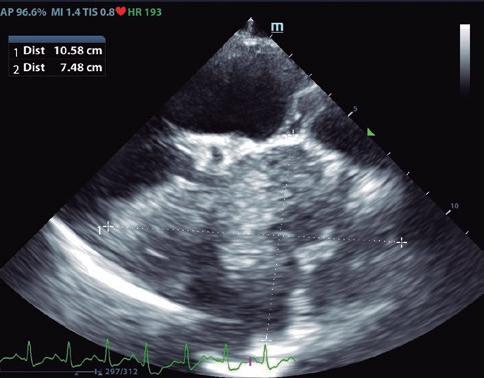

54 Enfermedades renales agudas que contribuyen al deterioro de la función cardiaca

que contribuyen al deterioro de la función cardiaca